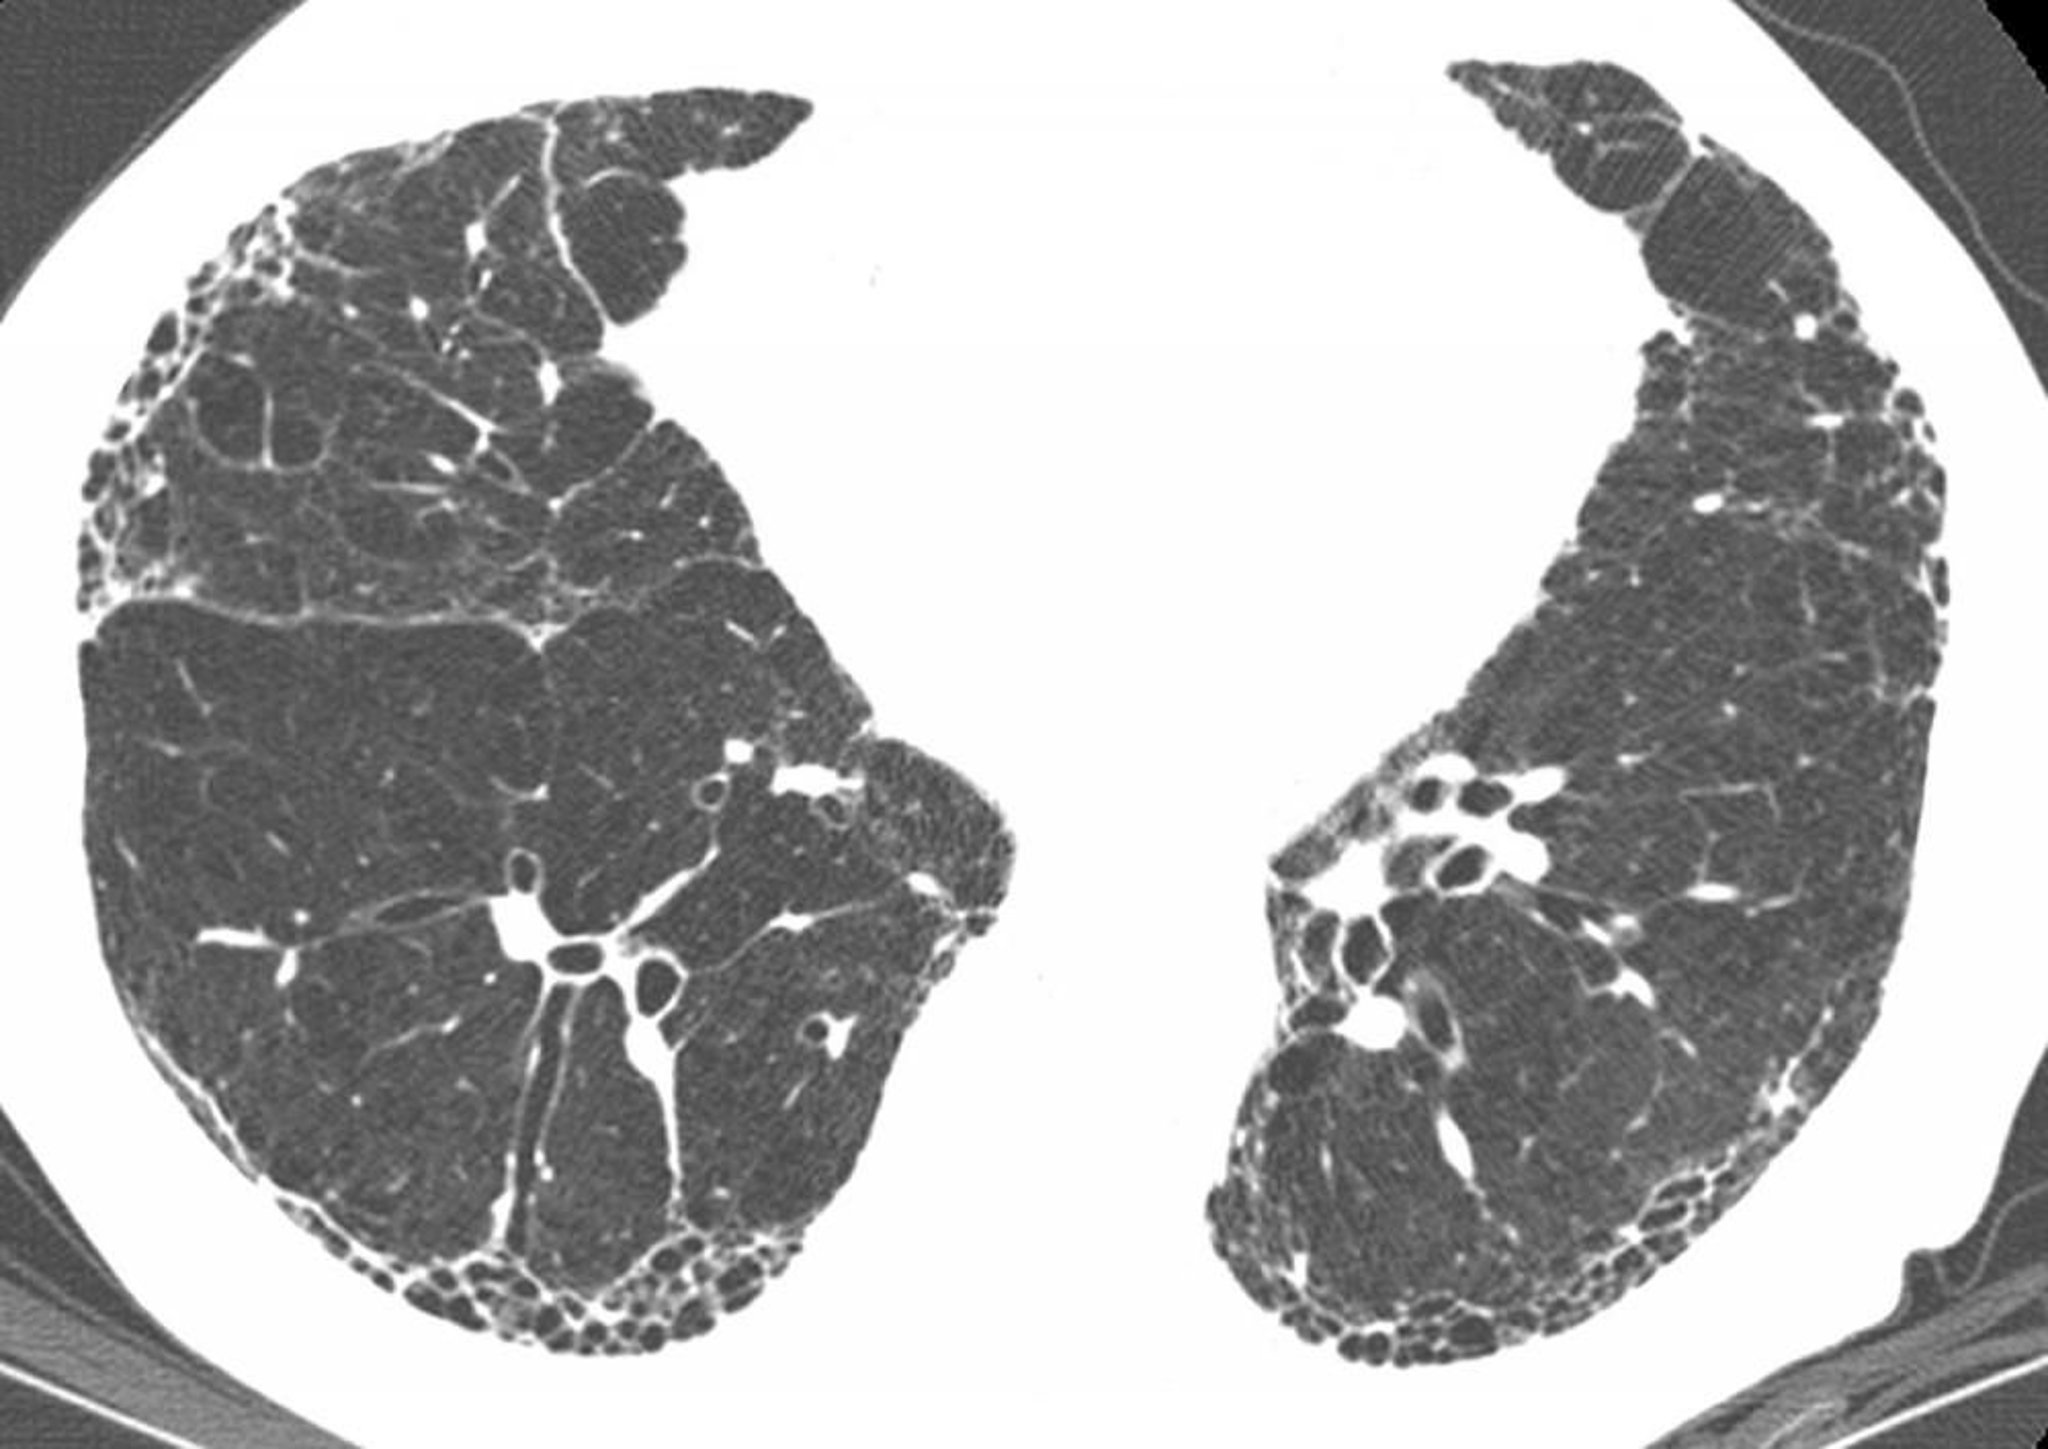

Subpleural honeycombing and traction bronchiectasis (signet ring sign, where multiple thickened dilated bronchi are seen below a pulmonary artery) are present on high-resolution CT in a patient with idiopathic pulmonary fibrosis (IPF). Findings inconsistent with IPF, such as nodules, are absent. These CT findings are virtually diagnostic of IPF if clinical findings are compatible.

Image courtesy of Harold R. Collard, MD.